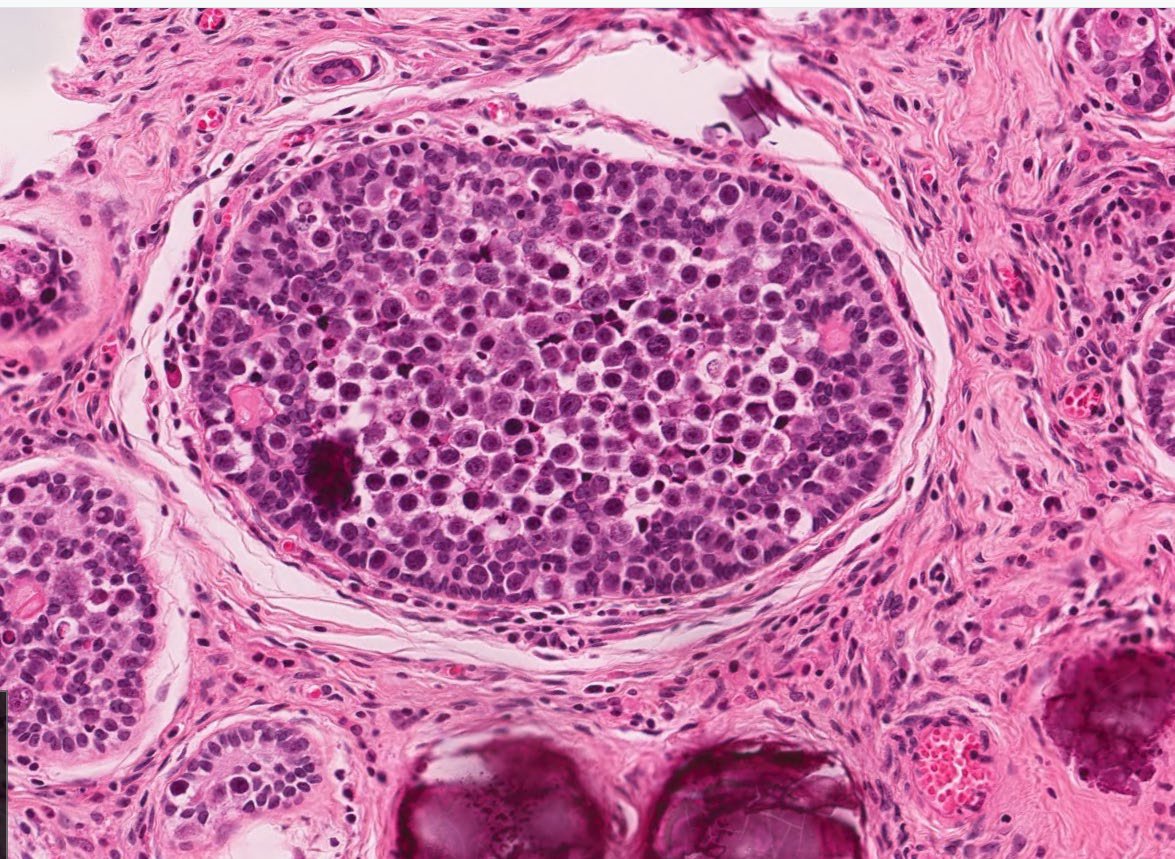

I am strongly associated with Disorders of Sex Development I can be seen in Undescended Testes I am benign but have a risk (8-10%) of undergoing malignant transformation. Who am I? 🤔 📸 Credit: Robert O Brady, MD #pedipath #peds #endocrine #pathx